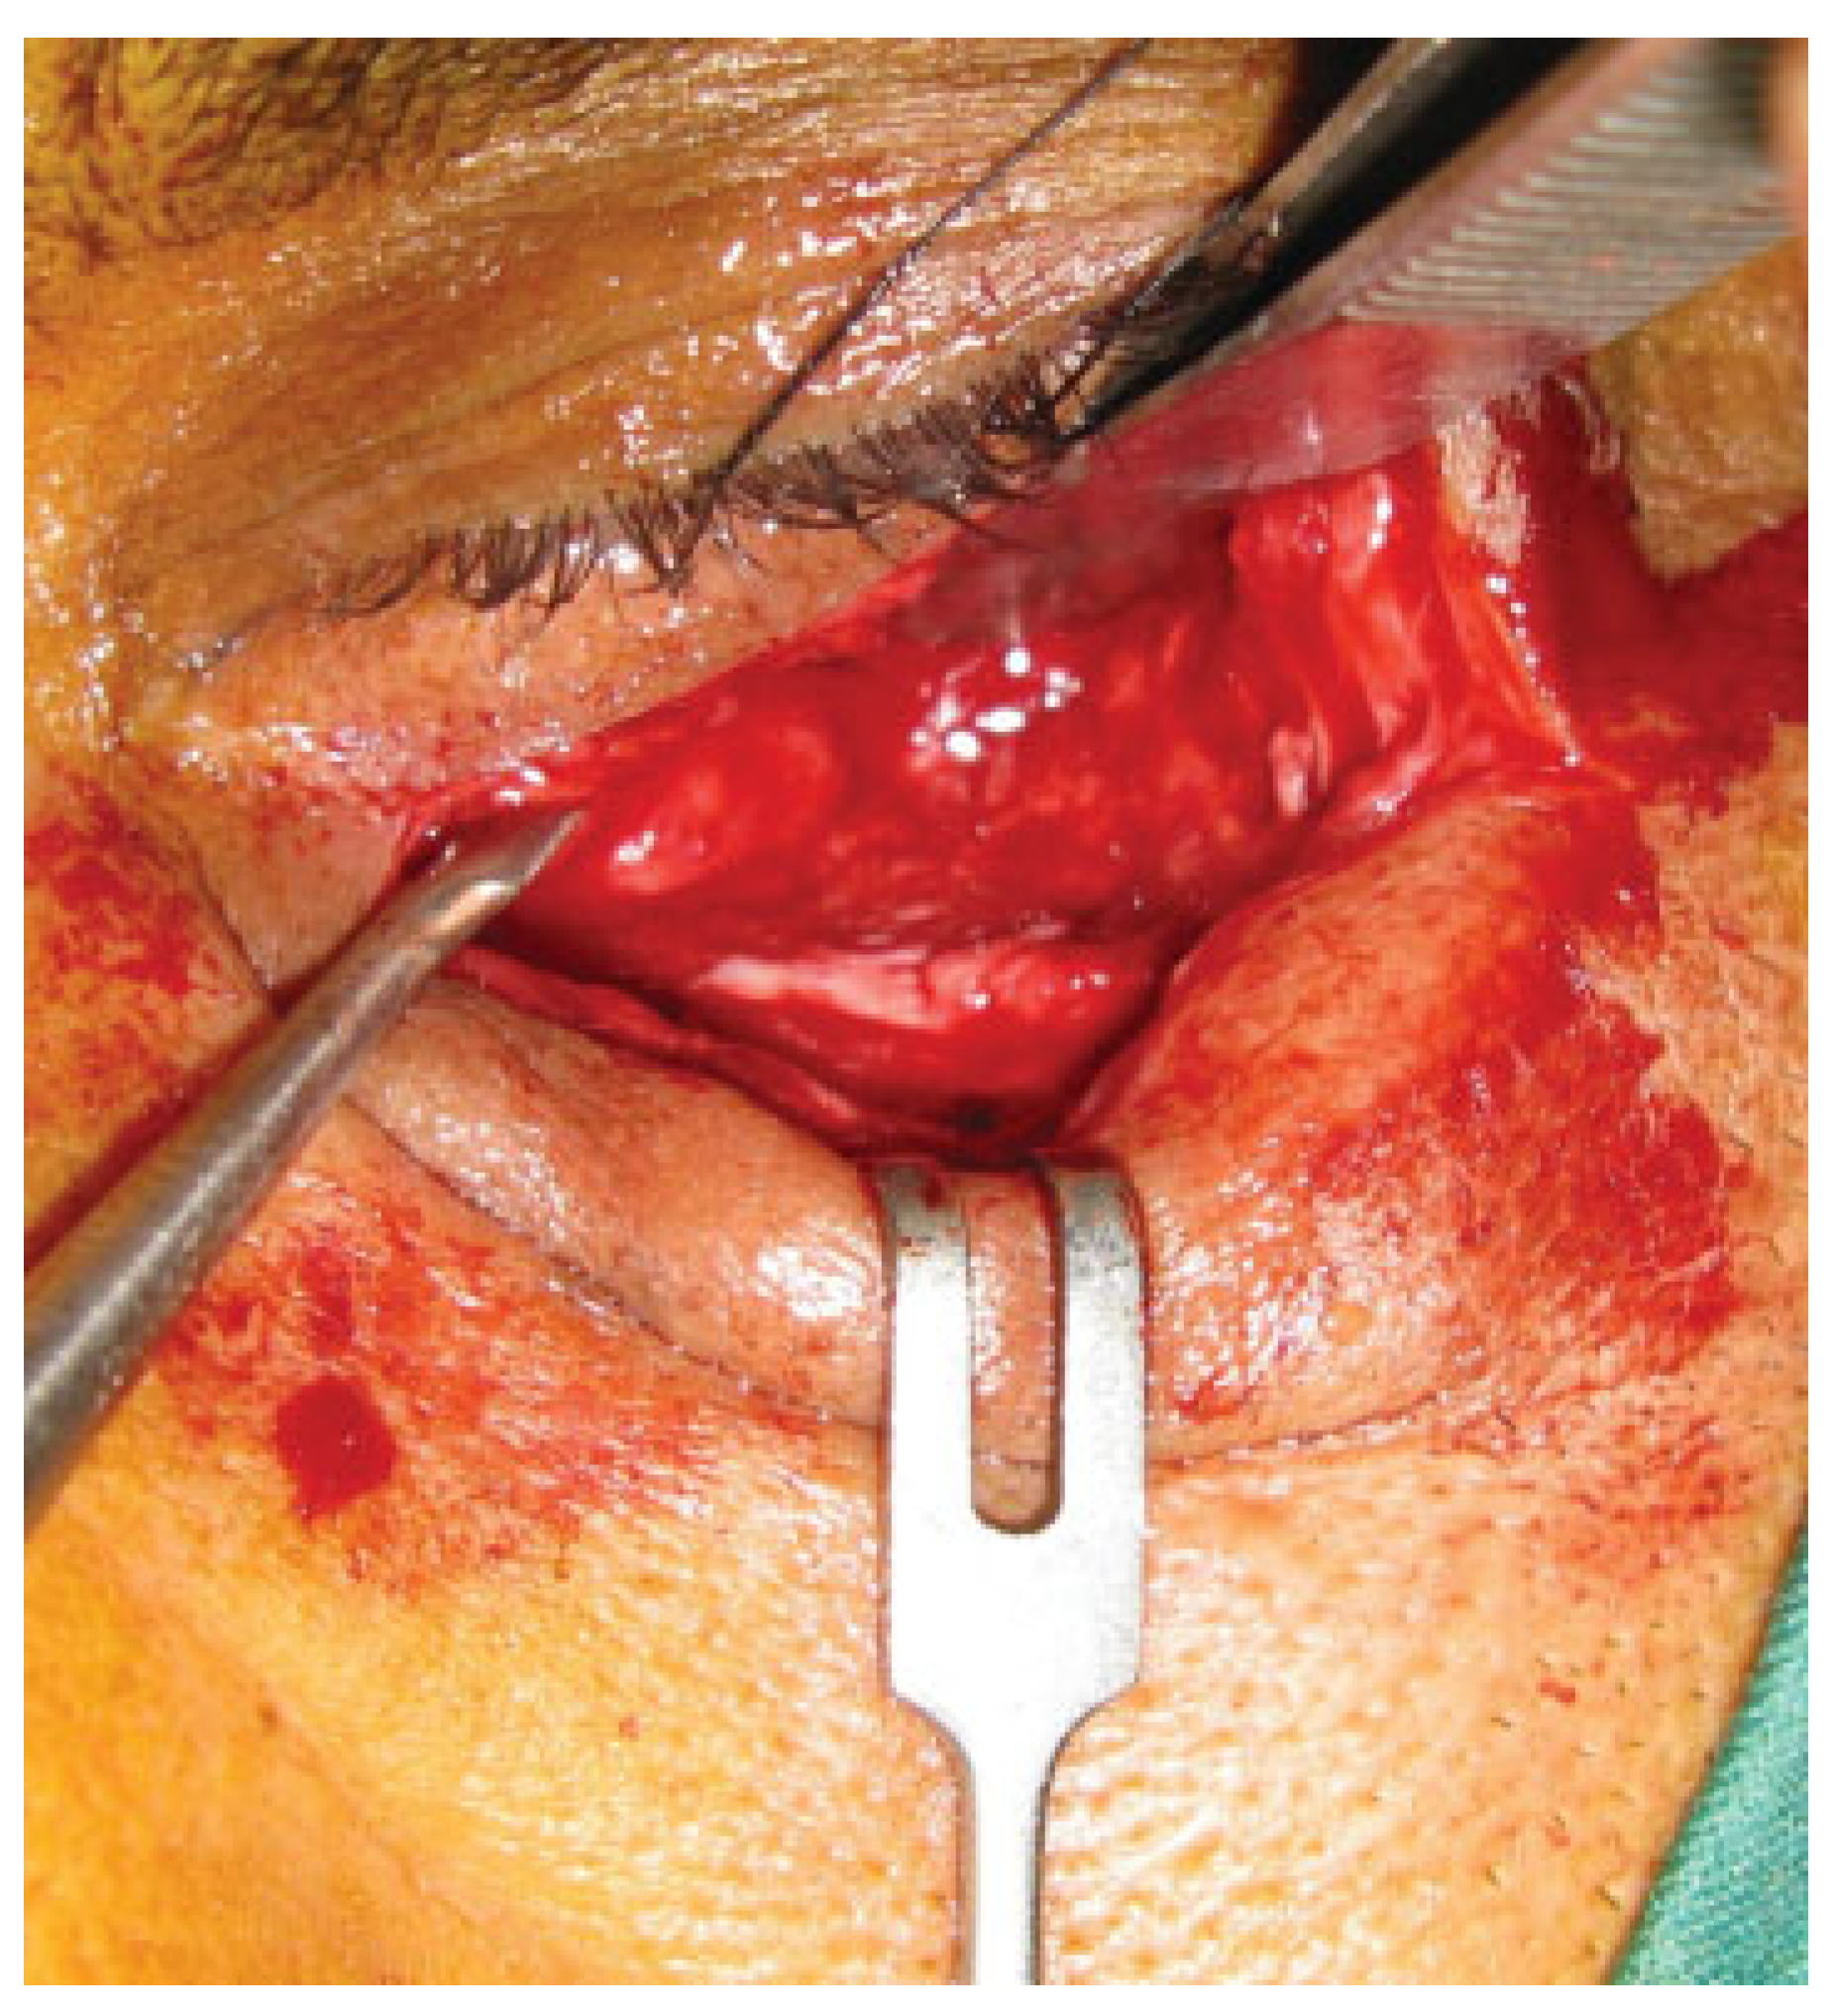

In this prospective study different parameters using biode-gradable plates for reconstruction of the blow-out fractures were assessed. The study was approved by the research committee of the medical ethics group of Shiraz University of Medical Sciences. The study sample was derived from the patients who referred to the Department of Craniomaxillo-facial Surgery for evaluation and management of orbital fracture between January 2009 and December 2010. Patients eligible for study inclusion had an impure blow-out fracture and there was a need to repair orbital floor and to fix the zygomaticomaxillary complex in a proper position. Patients who had pure blow-out fracture or minimal bone displace-ment in computed tomography (CT) scan views without the enophthalmos or the diplopia were excluded from the study. All the patients had a recent trauma and subsequently surgi-cal intervention was made between 1 and 10 days. A consul-tation was made with ophthalmologist before the surgical intervention. An axial and coronal CT scans were taken through 2-mm cuts for each patient before surgical interven-tion, immediate, and 18 months after surgery (Figure 1 and Figure 2). The amount of the orbital floor defect was measured in each case through CT scan. The surgical approach consisted of mid-lower incision for accessing the orbital rim and floor. Bone reduction and reconstruction was made through biode-gradable plate (PG910/PDO) (Figure 3). Titanium miniplates and screws were used for fixation of fractured infraorbital rim. The thickness of the biodegradable plates (PG910/PDO) was 0.5 mm. All the patients underwent secondary interven-tion to remove the titanium miniplates after 18 months. The orbital floor was reevaluated during the secondary interven-tion. The evaluation of remnant defects and biodegradable plates (complete or partial resorption) was made for every patient (Figure 4).

Figure 1. A coronal view shows the left zygomatic mandibular fracture with the blow-out fracture.